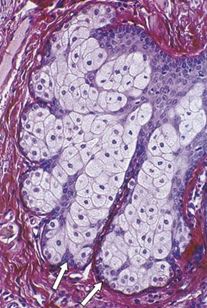

特点二:头皮上的皮脂腺密度大约是144-192个/平方厘米 ,额头上的大约是52-79个/平方厘米,脸颊上的则大约是42-78个/平方厘米[2]。

这也就是说,即使是跟面部最容易出油的额头相比,头皮的皮脂腺数量也有它的2倍之多,下图为皮脂腺电镜图。